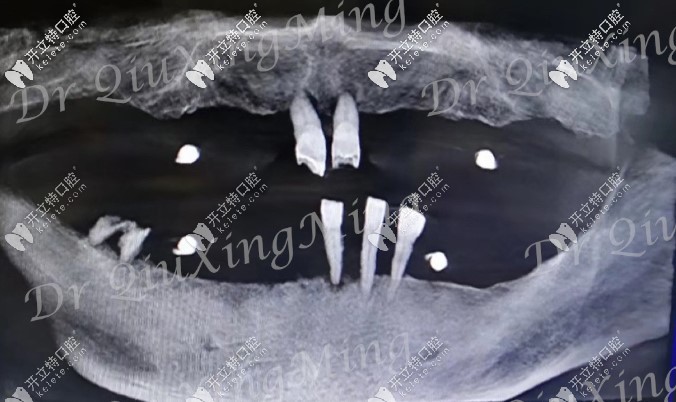

大爺口腔CT照

檢查顯示他的牙槽骨有部分吸收,一般的種植手術(shù)是需要植骨的,但邱醫(yī)生給他用的是all-on-4種植技術(shù),不用植骨,還可以選擇即拔即種的修復(fù)方式。